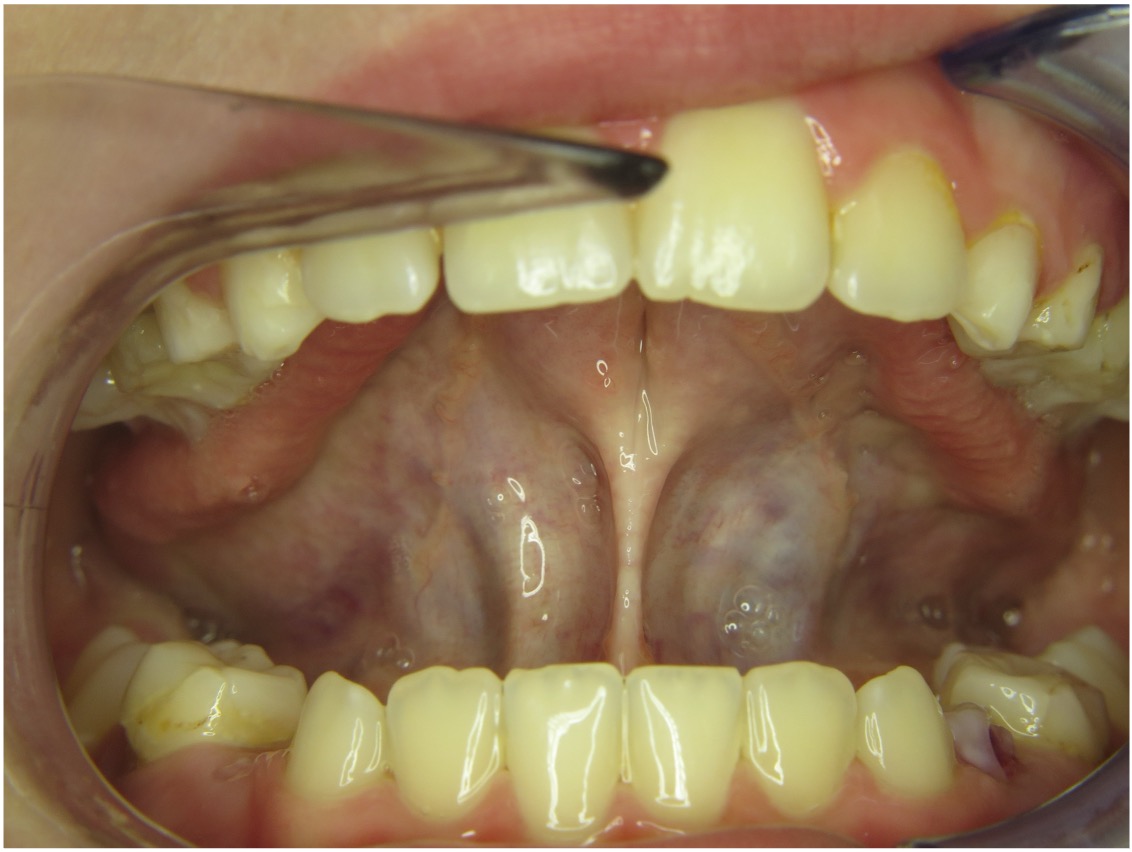

Wir sagten es bereits an anderer Stelle – Bilder sagen mehr als 1000 Worte…

Die Galerie zeigt verschiedene Problemstellungen unserer Patienten von Anfang bis Ende:

mykie® macht’s möglich – sehen Sie selbst: